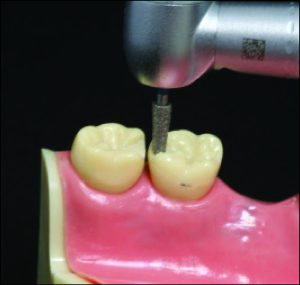

Throughout the mouth preparation process, the diagnostic model should be with the dentist on the analyzer table, positioned at the appropriate inclination to the path of insertion. Thus, the relationship between the diamond bur and the tooth surface to be shaped is projected from the model into the mouth (Figure 10-18).

a) The relationship between the tooth surface shaped in the diagnostic model on the analyzer table and the bur.

b) Preparation made by projecting the relationship between the bur and the model into the patient's mouth.